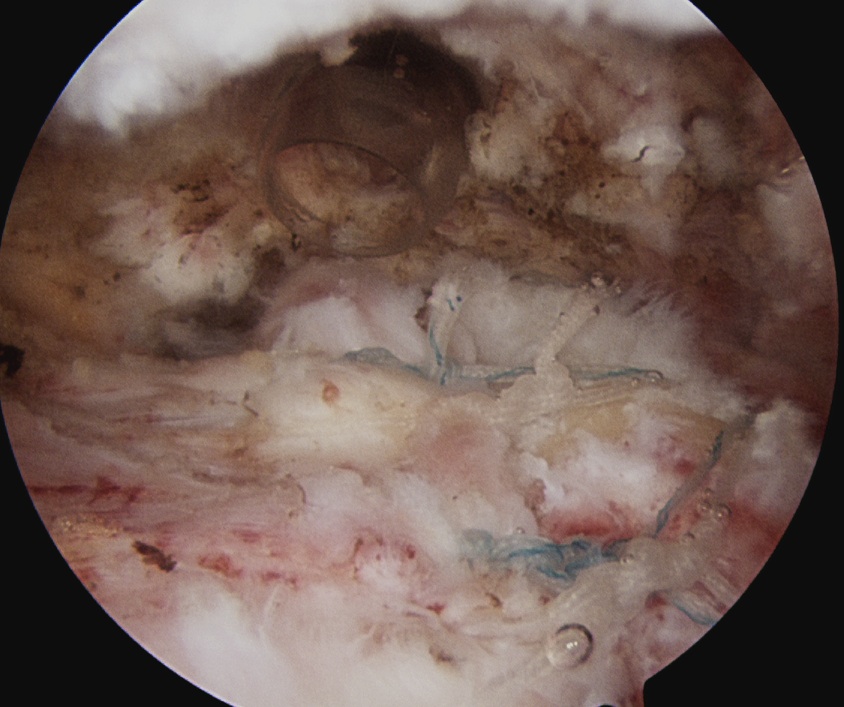

D. Transosseous equivalent / suture bridge

Technique

- biomechanically replicate tradional open transosseous

- sutures crossed as below in double row

- aiming to increase contact between cuff and footprint

Tie sutures

- posterior to anterior / anterior to posterior

Double row

- either pass second lateral row of anchors or

- use foot print anchors, retrieve previous sutures

- can make suture bridge configuration

- check repair via lateral portal